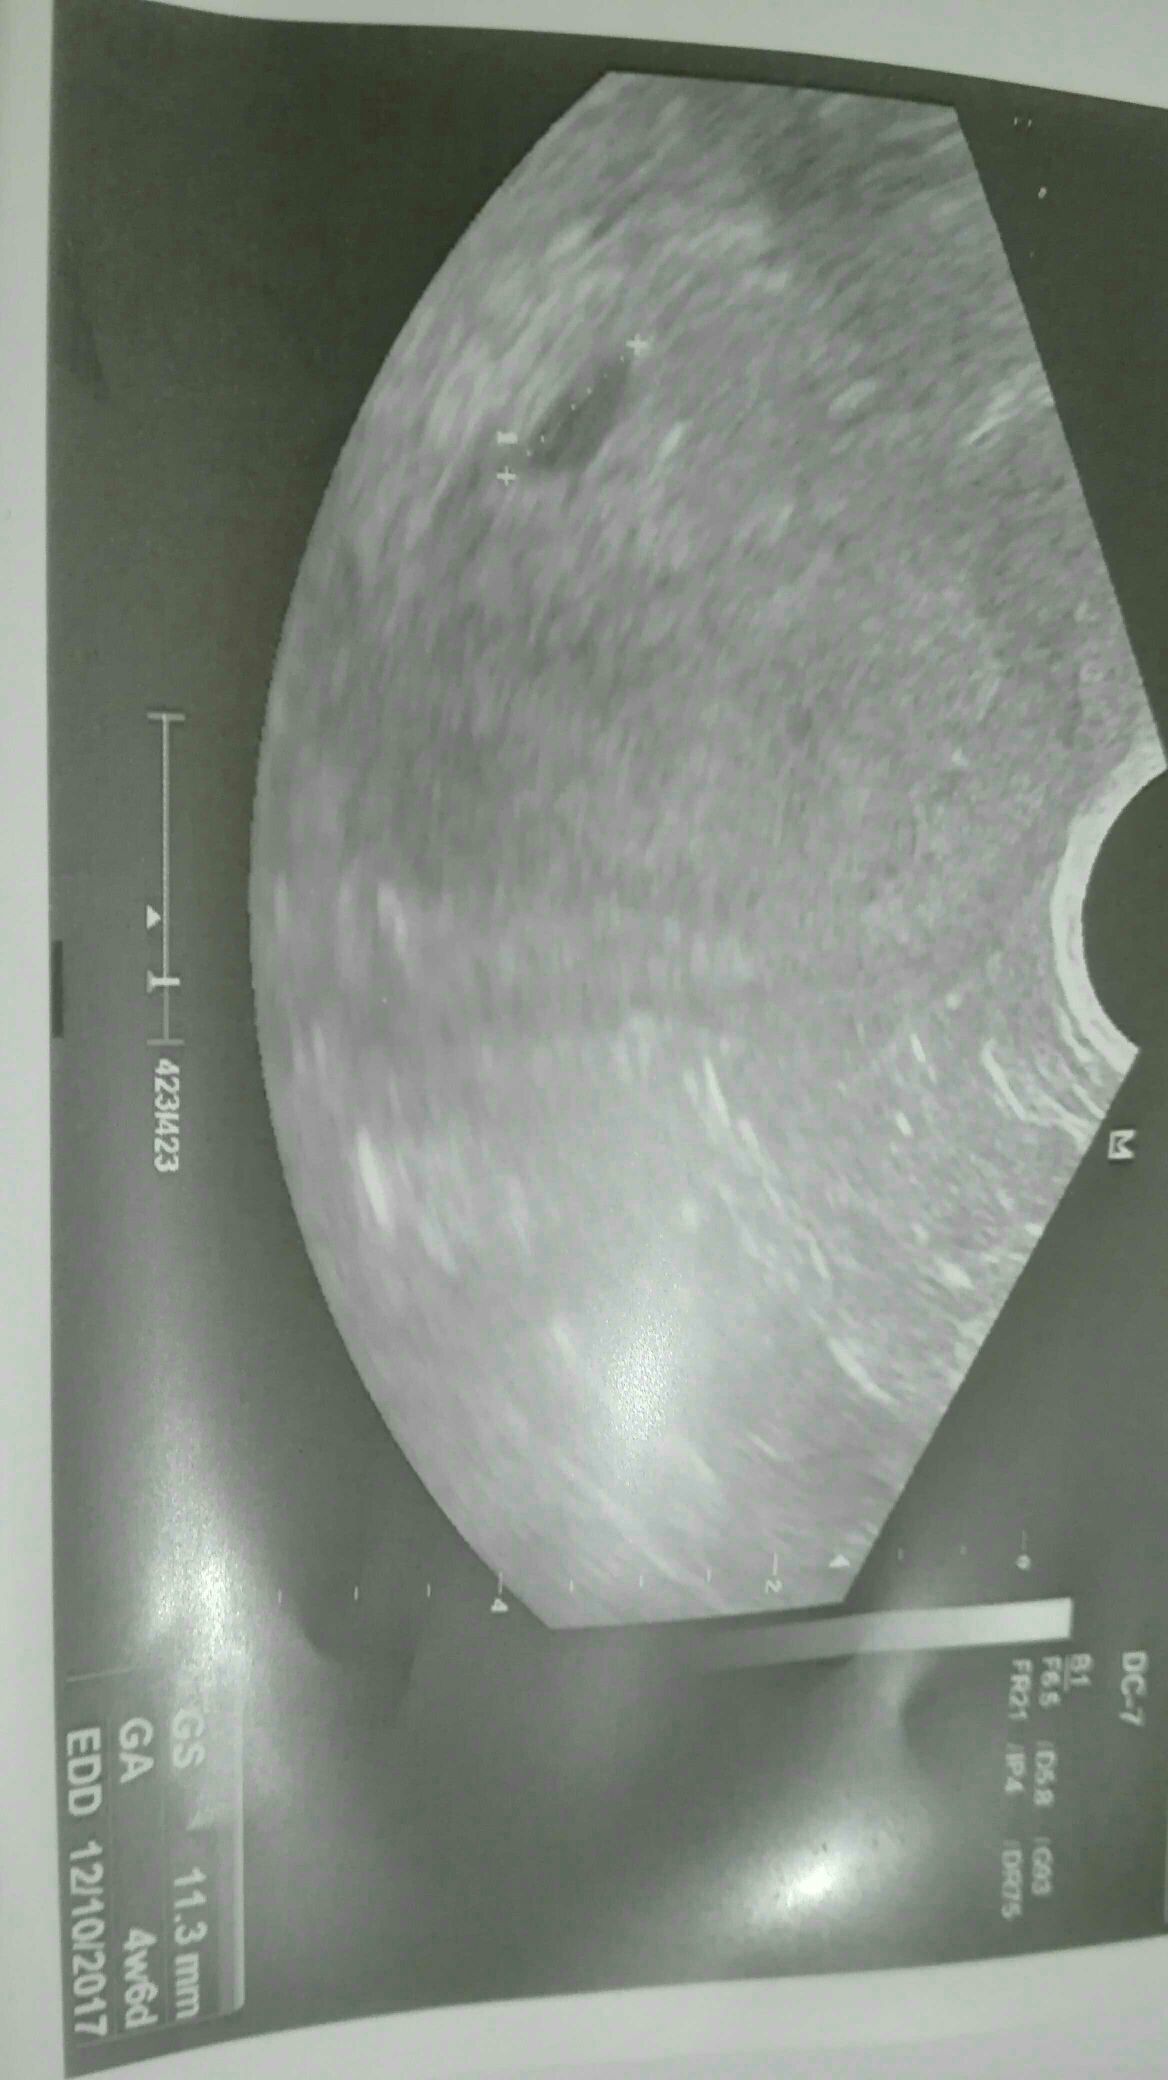

Wracam od lekarza, pecherzyk ma 11, 3 mm w srodku nic nie widac. 20 -stego mam na kontrole jechac. Wg usg to 4t,6d a ja dzis mam 5t6d.

I by sie kochana zgadzało ptrz 5t6d pęcherzyk 11mm , dzidzia 3mm ale zapewne za słabe usg i nie dowiedział dzidzi masz fotke [emoji6]